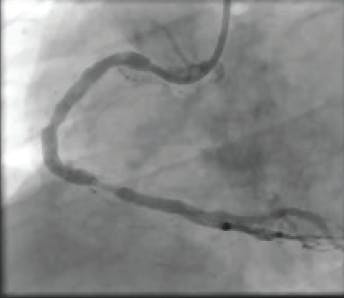

A radial approach was used for intervention. The diagnostic catheter revealed a totally occluded RCA with acute stent thrombosis and TIMI 0 flow (Figure 1). Using a whisper wire, the lesion was crossed. Two runs were then performed using CAT RX, which resulted in establishment of flow (Figure 2 and Figure 3). Subsequently, balloon dilatation was performed in the stent with a 2.5- X 20-mm compliant balloon; a 3.5- X 38-mm Resolute Onyx™ stent (Medtronic) was deployed in the mid-RCA distal to the original stent and was postdilated with a 4- X 15-mm noncompliant balloon. TIMI 3 flow was noted postprocedure, with grade 3 myocardial blush (Figure 4).

Figure 3. Angiogram following aspiration with CAT RX.

Figure 4. Final angiogram with complete TIMI 3 flow after the use of CAT RX.